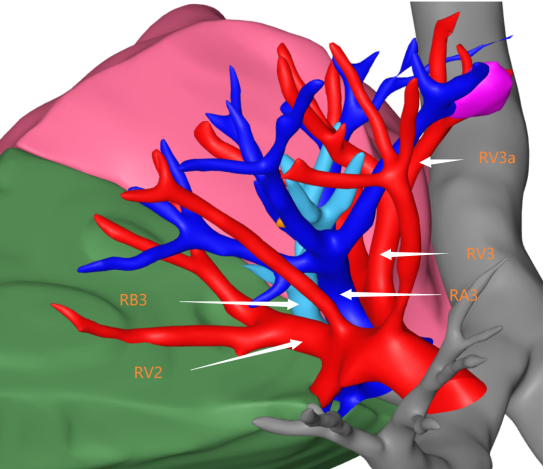

一次感冒,发现双肺结节 患者李女士:“我是由于一次感冒,在老家拍摄胸部CT后发现有双肺结节,后来在家人的陪同下来到市第二人民医院就诊。经过王述波主任团队的手术治疗,顺利地切除了结节,不再担惊受怕了。” 在发现肺结节1个月后,李女士被王述波主任手术团队接诊。团队进行评估发现,该患者CT提示右肺上叶毛刺状结节、左肺上叶混合密度结节,考虑早期肺肿瘤可能性大。(右肺上叶前段结节;左肺上叶上舌段结节) “量体裁衣“精准手术,术后4天康复出院 王述波、王永明主任团队在胸外手术规划系统的指导下,经过术前评估和讨论,决定采取分阶段的手术方案以最大程度地确保手术的成功和患者的安全。 首先,对患者右肺上叶前段采用肺段切除手术进行优先处理。利用系统提供的精准定位功能,准确识别结节周围的血管位置、安全切除范围。术中,在胸腔镜下准确裁剪,保证切缘,确认切除了患者右肺上叶前段肺组织。 最终这例手术过程顺利,术后患者4天康复出院,没有不良反应。(右肺上叶前段病灶阻断血管三维重建图) AI+3D助力手术,消除患者后顾之忧 潍坊市第二人民医院(潍坊呼吸病医院)2024年初引进的3D手术规划系统,为每位患者量身定制了精准的手术方案,在AI+三维重建技术的加持下,为实现精准的肺段及肺亚段切除提供了强有力的支持,达到“量体裁衣”的目的。在术前患者能够清晰了解治疗过程,解除了早期肺癌可能带来的焦虑感,使得治疗过程更加透明和可信。 健康之路,我们与您同行 潍坊市第二人民医院(潍坊呼吸病医院)胸外科是市级医学重点学科,全科医护人员以学科建设、新技术引进和创新为切入点,加强人才培养和引进,现已形成集医疗、教学、科研于一体,具有明显特色和优势的学科。近年来,胸外科开展了气管支气管成形术,肺、食管联合切除手术、单孔胸腔镜肺叶切除、单孔胸腔镜肺段切除、胸腔镜下袖式切除、人工胸骨移植手术、食管癌二切口、三切口,二、三野淋巴清扫等一系列高难度手术,居国内领先水平。由胸外科领衔的肿瘤综合治疗会诊制度,涉及到胸外、呼吸、肿瘤内科、放疗科、放射科等多个专业,对每一位胸部肿瘤患者就诊断、鉴别诊断、治疗及预后等方面进行多学科会诊,受到了全市乃至全省专业同行的认可。咨询电话:0536—8214091/8214109 科普链接 胸腔镜下肺段切除术胸腔镜下肺段切除术,又称胸腔镜下解剖性肺段切除术,采用微创方式将小病变所在的肺段精准切除,在保证肿瘤手术根治的同时,最大限度保留了正常的肺组织,降低了肺功能的损失,实现了真正意义上的微创。